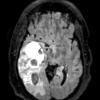

NEOPLASMS (GLIAL)

Glioblastoma, adenoid pattern (9)